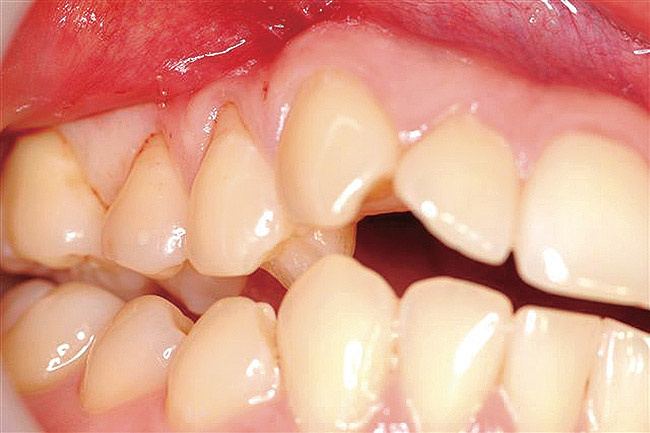

The patient presented with gingival recession and a complaint of cold sensitivity in the maxillary first and second bicuspid teeth (Figure 14). Minimal attached gingiva was noted. A connective tissue graft was placed to widen the band of attached gingiva and eliminate the cold sensitivity present presurgically (Figure 15).

Figure 14  Gingival recession on the first and second maxillary premolars with a thin band of attached gingiva.

Figure 14